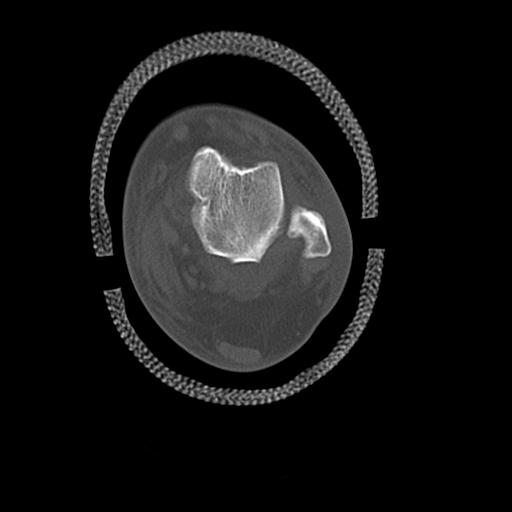

49554 3/13 膝 4R 3/16 4R 1/18 2R 78歳男性 膝蓋骨骨折